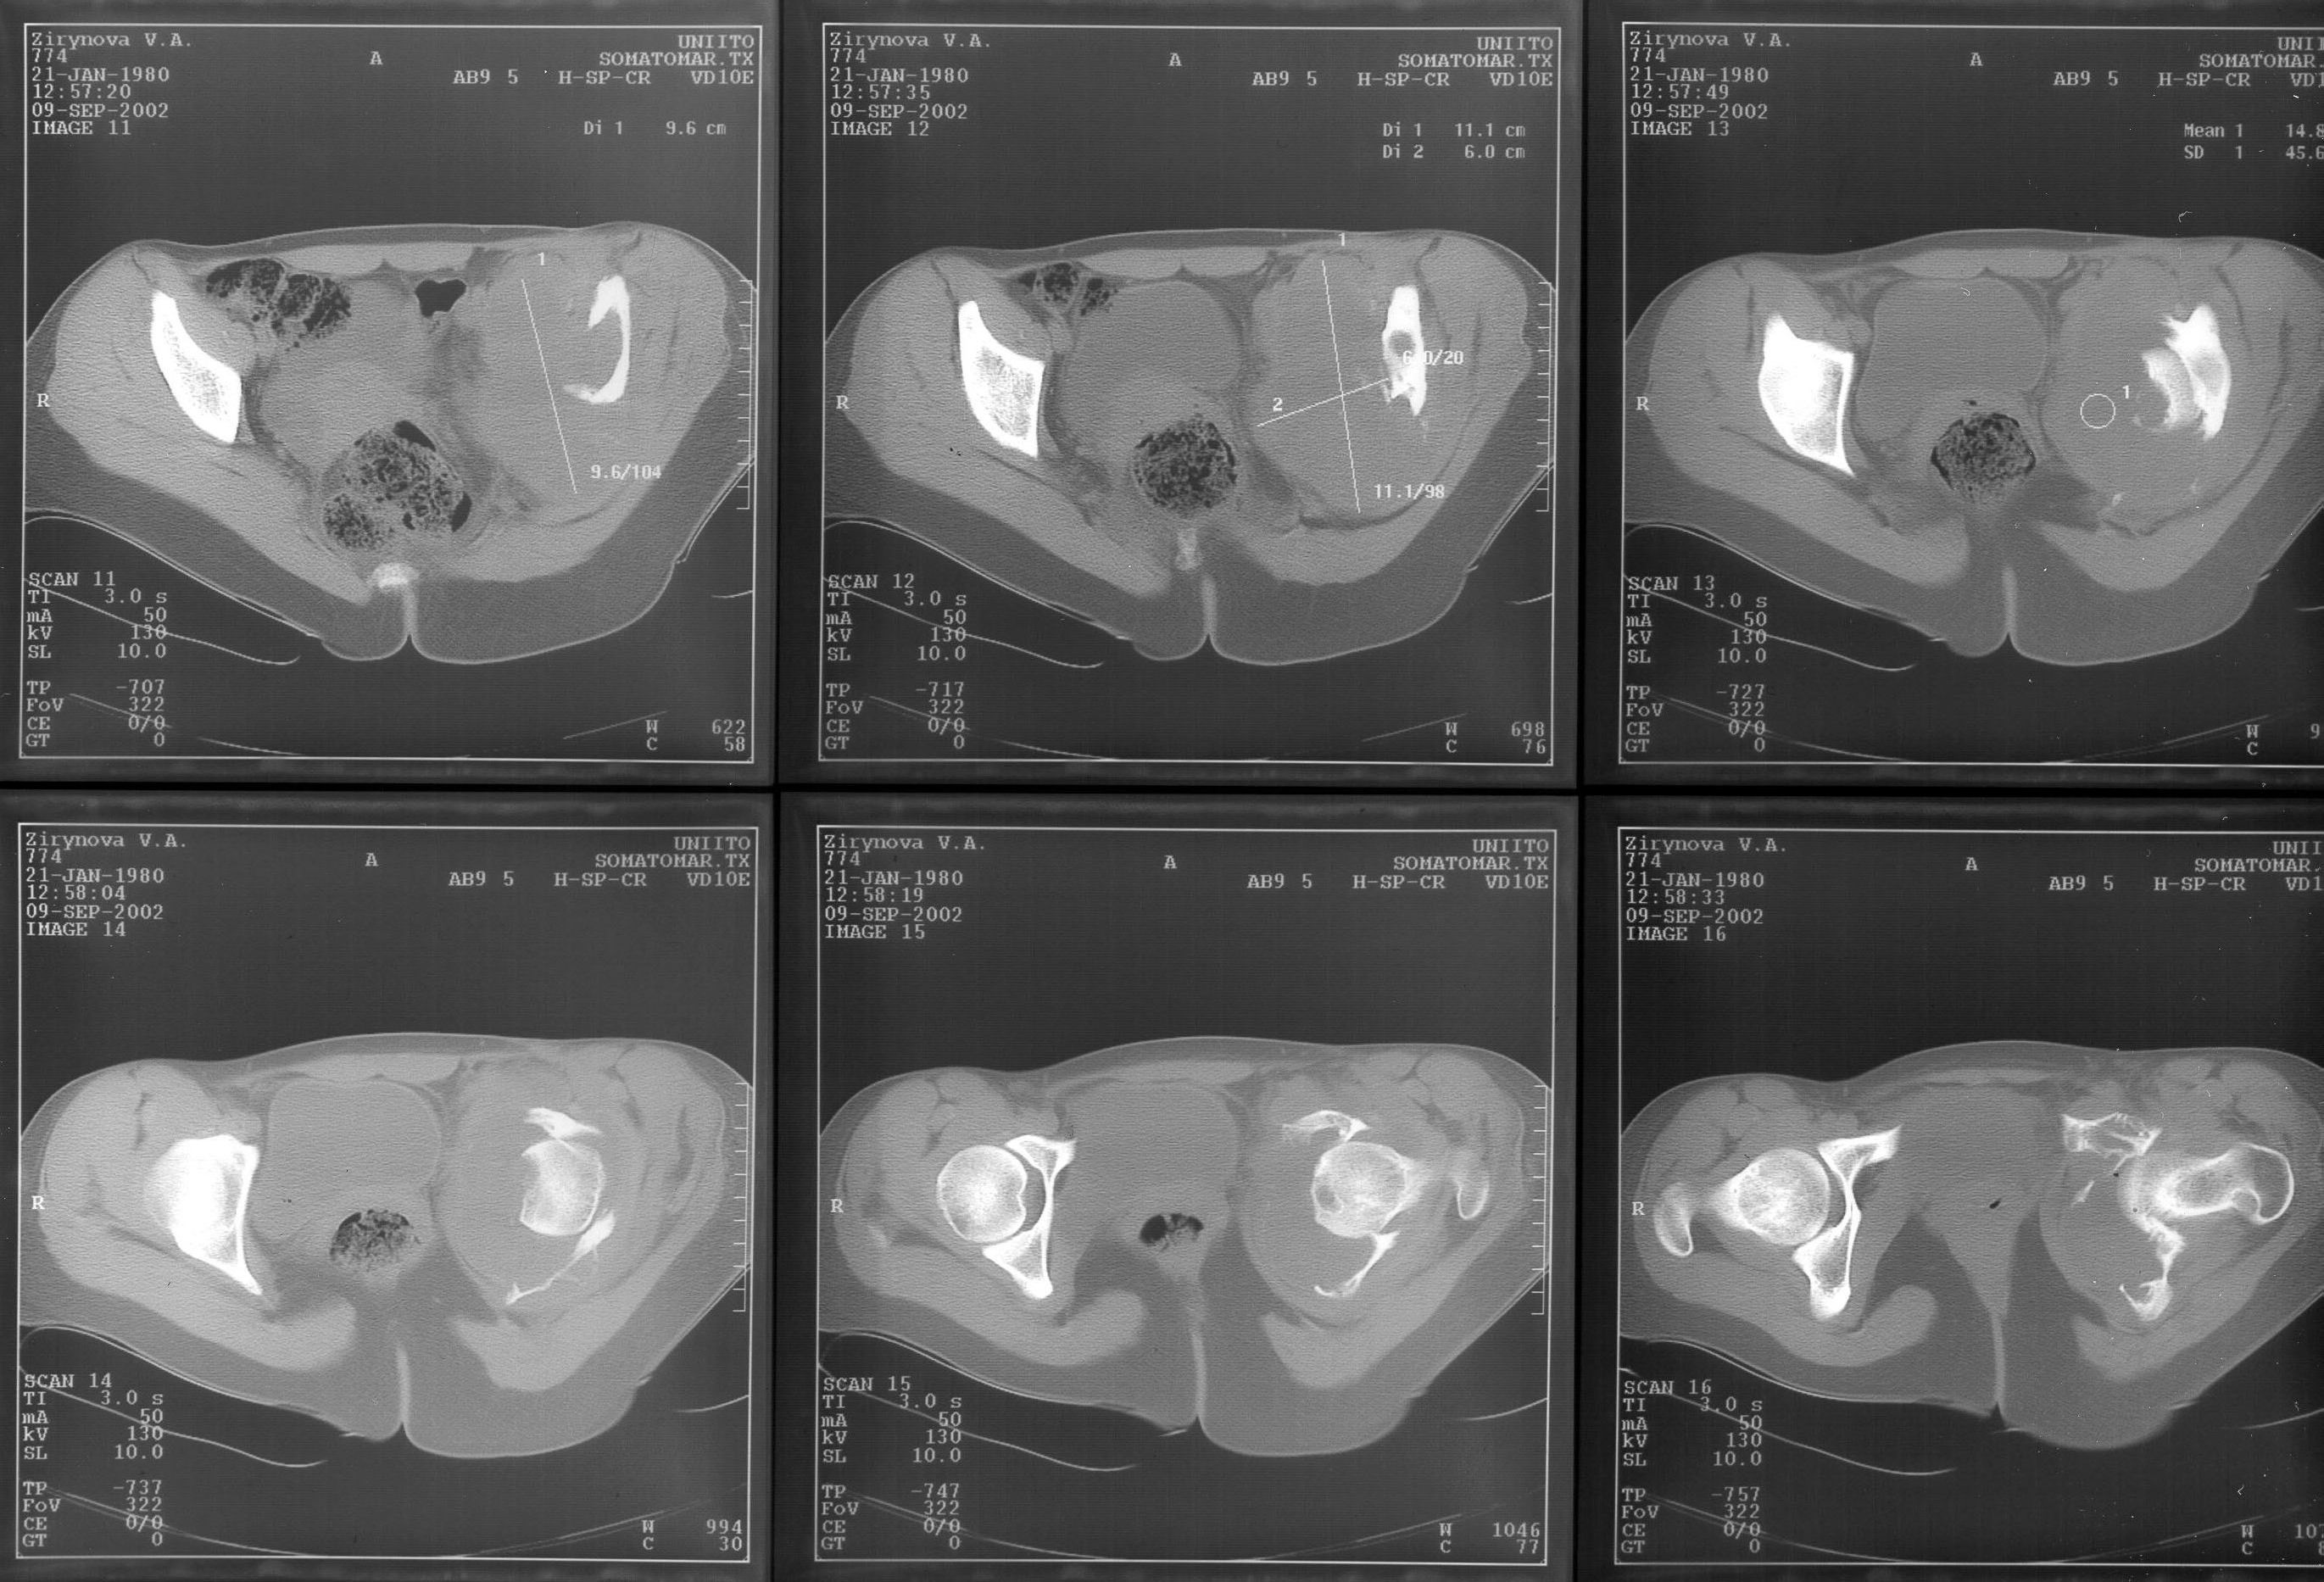

Имеющиеся КТ выложены тут и тут.

looking to the X-rays and CT scan it appears this young lady has an aggressive bone leasion.

I completely agree with Christian Veillete concerning differential diagnosis. There is necessary to perform biopsy to evaluate the tumor and its histological degree. Also should be done three dimensional CT scan and MRI to evaluate the precise lack of the bone tissue and involvement of surrounding tissues.

The X-ray and CT scan appearance is likely as the chondrosarcoma what is seldom but common

finding in the replacement surgery of the hip. Having precise histological, CT and MRI data should be planed the amount of surgery after detailed discussion with patient. There is no any possibility to perform primary replacement. If there is the chondrosarcoma hemipelvectomy would be the most live saving procedure. If there is an aggressive giant cell tumor or other findings about allografting, reconstructive surgery with custom made implant or saddle modular prostheses (W.Link) could be discussed. In other wards there are so many different thinks what should be discussed with patient